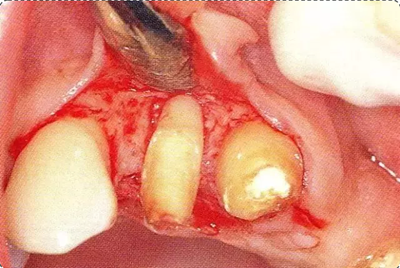

圖10-1

遠中部有8mm的牙周袋。上頜前牙部等需要考慮審美性的部位進行GTR法,但也可能會出現(xiàn)齦瓣壞死導致牙齦乳頭喪失,反而導致審美性變差的情況。

深牙周袋的治療

圖10-3  考慮到審美性,應用牙齦乳頭保存術(Papilla preservation technique),進行了自體骨移植。